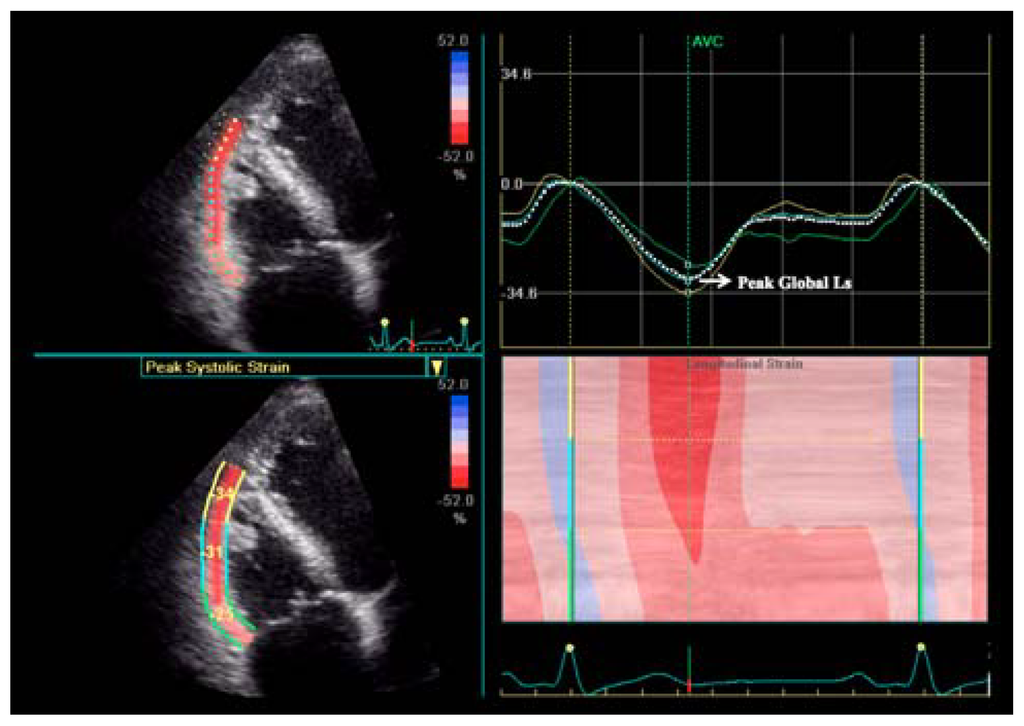

Deformation imaging by STE is a new echo technique that has been developed to assess left ventricular myocardial deformation. Nevertheless, recent studies have demonstrated its feasibility in measuring RV strain (Figure 1) to detect RV myocardial function changes in several pathological conditions [,,,,,,,,]. Compared to Tissue Doppler Imaging, STE is an angle-indipendent technique based on internal reference, thus, avoiding limitations related to translational cardiac motion. Preliminary researches showed good correlations with the other standard echo parameters of RV function, in particular with TAPSE []. Among non-volumetric echo parameters, RV free-wall strain by STE demonstrated the closest correlation with RV ejection fraction measured by CMR [].

Figure 1.

Right ventricular longitudinal strain by two-dimensional speckle tracking in a healthy subject. Upper right: longitudinal strain dotted curve showing the main values. Ls = longitudinal strain.